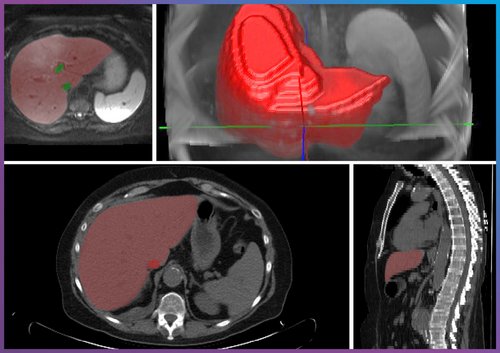

The liver has long been important in medical imaging. For example, it has been used to detect and characterize lesions, assess parenchymal changes, and plan minimally invasive procedures. Although high-resolution CT and MRI data provide a wealth of information, evaluating this data remains challenging. This is precisely where our technological focus comes in.

At Chimaera, we develop solutions that support the entire data-driven analysis process. Our offerings include precise annotations for AI training datasets, automated or semi-automated segmentations, and interactive 3D visualizations that allow clinical teams to intuitively explore complex structures. These tools provide a foundation for more reliable detection and quantification of pathological changes, including fat content determination, tumor segmentation, and volumetric analyses for surgical planning.